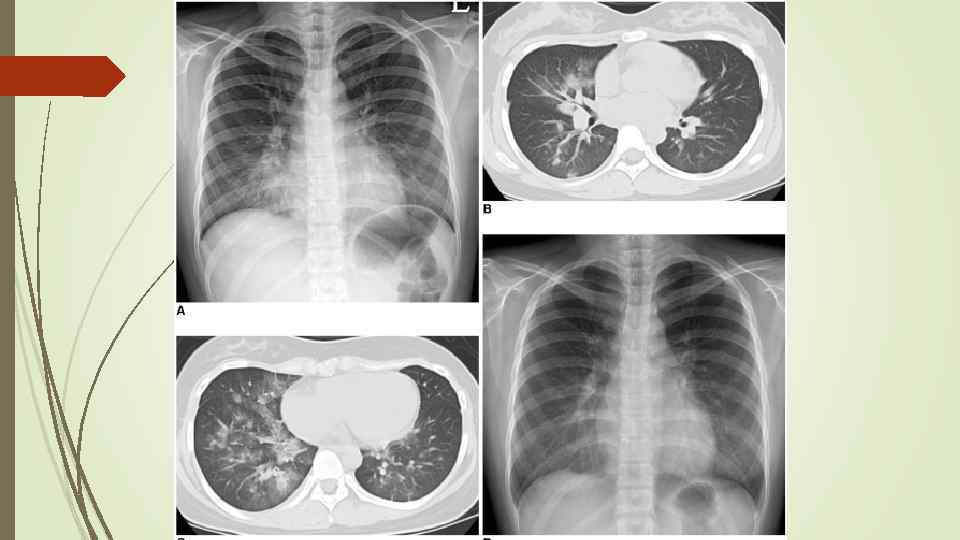

Бронхопневмония Характерно наличие двухсторонних множественных очаговых теней. Контуры очагов нечеткие, интенсивность тени небольшая. Инфильтрация неоднородна. Мелкие, малоинтенсивные очаги не всегда выявляются на снимках. Легочный рисунок усилен на всем протяжении легких. Корни расширены, не структурны. Как правило, отмечается реакция плевры, могут быть и экссудативные плевриты.

Бронхопневмония Характерно наличие двухсторонних множественных очаговых теней. Контуры очагов нечеткие, интенсивность тени небольшая. Инфильтрация неоднородна. Мелкие, малоинтенсивные очаги не всегда выявляются на снимках. Легочный рисунок усилен на всем протяжении легких. Корни расширены, не структурны. Как правило, отмечается реакция плевры, могут быть и экссудативные плевриты.

bronhopneumoni

bronhopneumoni